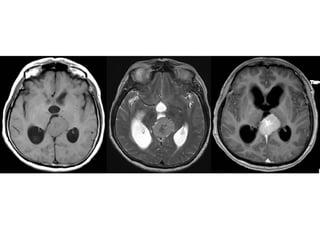

a)Sagittal T1 weighted MR

image shows an

heterogeneous pineal region

mass with foci of T1

shortening due to

hemorrhage , note the

associated hydrocephalus

b)Axial postcontrast T1-

weighted MR image shows

that the pineal region mass

also has an heterogeneous

enhancement with foci of

necrosis/cyst , involvement of

the tectal plate and both

thalami are also present (not

shown) , evaluation of serum

oncoproteins demonstrated

high level of b-hCG , biopsy of

the lesion revealed that it

corresponds to

Choriocarcinoma

a)Sagittal T1 weightedMR image shows an heterogeneous pineal region mass with foci of T1 shortening due to hemorrhage , note the associated hydrocephalus b)Axial postcontrast T1- weighted MR image shows that the pineal region mass also has an heterogeneous enhancement with foci of necrosis/cyst , involvement of the tectal plate and both thalami are also present (not shown) , evaluation of serum oncoproteins demonstrated high level of b-hCG , biopsy of the lesion revealed that it corresponds to Choriocarcinoma